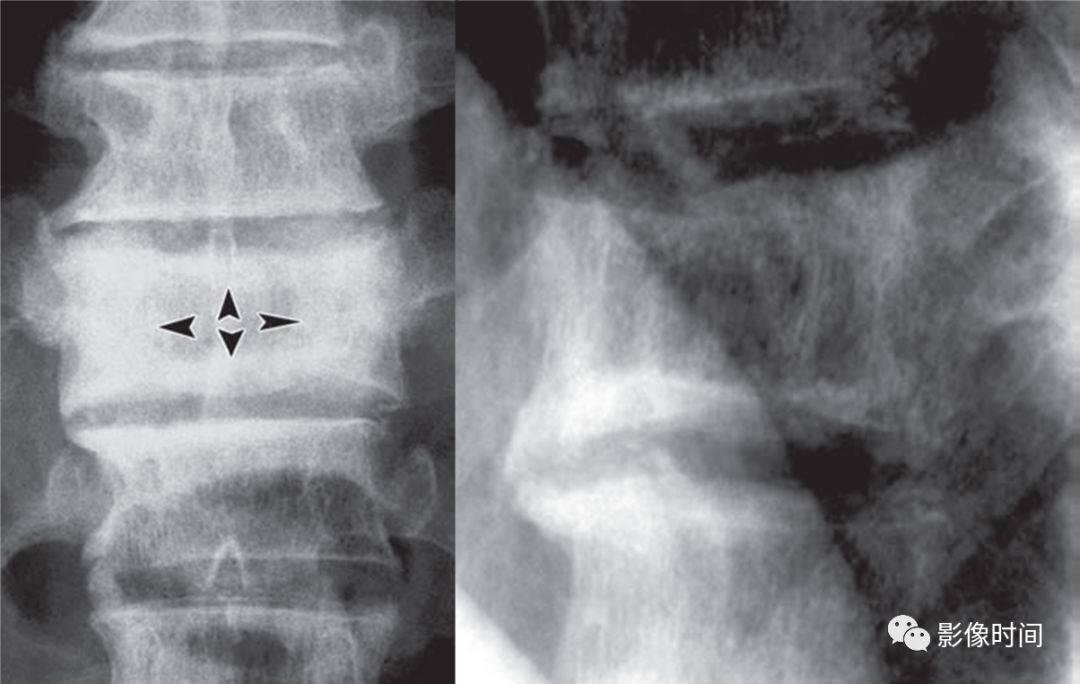

5倒置拿破仑帽征

倒置拿破仑帽征(inverted napoleon hat sign),亦有译为反拿破仑帽征

倒置拿破仑帽征是指在腰椎正位 X 线片中,腰 5 与骶 1 的投影轮廓重叠,形似倒置的拿破仑帽(蓝箭)。其中帽子的边缘是腰 5 的横突形成,而帽子的圆顶是由腰 5 的椎体投影构成。

本征象主要用于描述腰 5 椎体前滑脱(这种滑脱通常为先天性或创伤性,退变性的少见),在腰 5 未滑脱但腰骶部显著前凸时也可以出现此征象。

典型病例

22 岁男性,腰椎侧位片可见腰 5 椎体呈梯形(黑箭头),显著向前、下滑脱(黑箭),正位片形成倒置拿破仑帽征(白箭)。

7双棘突征

双棘突征(Double spinous process sign),又称幽灵征(ghost sign)

双棘突征是指在颈椎正位片上,一个棘突的投影因为棘突骨折的关系变成了两个较小的棘突投影,两者紧邻,上下分布(黑箭)。本征象用于描述铲土者骨折,多见于颈 6 和颈 7 的棘突,亦可见于上部胸椎棘突。

铲土者骨折,正位 X 线片示颈 7 呈现双棘突征(箭),提示颈 7 棘突骨折。